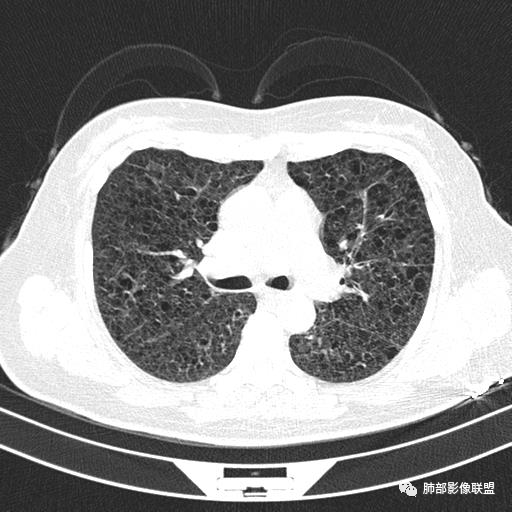

双肺弥漫囊腔,累及肋膈角,囊腔形态相对规则单一。

CT平扫示双肺弥漫分布大小不等囊状薄壁透光区,无内、中、外带分布差异,间质稍示增厚。拟LAM

中年女性育龄期妇女,咳嗽气喘,无吸烟史,有苯吸入史。影像:双肺弥漫均匀小囊腔,无明显分布优势,囊腔形态欠规则,壁薄,部分囊腔边缘血管征,伴双肺弥漫磨玻璃影,无结节,考虑lam,鉴别苯中毒肺损伤,囊腔多有分布优势,小叶中心分布为主,形态规整等

中年育龄期女性,双肺多发含气囊腔弥漫性分布,囊间肺组织结构正常,常规考虑Lam

CT表现:双肺弥漫大小不等的薄壁囊腔,囊壁<2mm,外形规则,血管影多位于囊腔周围,囊腔之间肺组织正常,随着疾病进展到晚期,囊腔变大、增多,不可胜数,囊腔可融合成较大的囊,与肺气肿相似,形成间质性肺纤维化。部分病例可出现结节影。